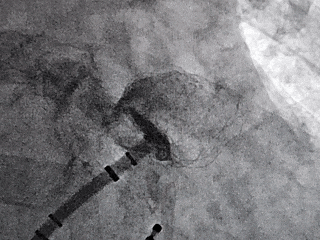

术中DSA肝位造影:大鸡翅型左心耳

心耳上缘内壁凹陷

肝位左心耳测量

开口24.97mm

深度25.25mm

MemoLefort封堵器展开后DSA下充分评估

释放后DSA下造影,多切面观察封堵左心耳开口无残余分流,且封堵器放置位置理想,充盈整个心耳开口处。

同时肝位、右肩位造影确认封堵器位置合适,无残余漏,左心耳完全封堵